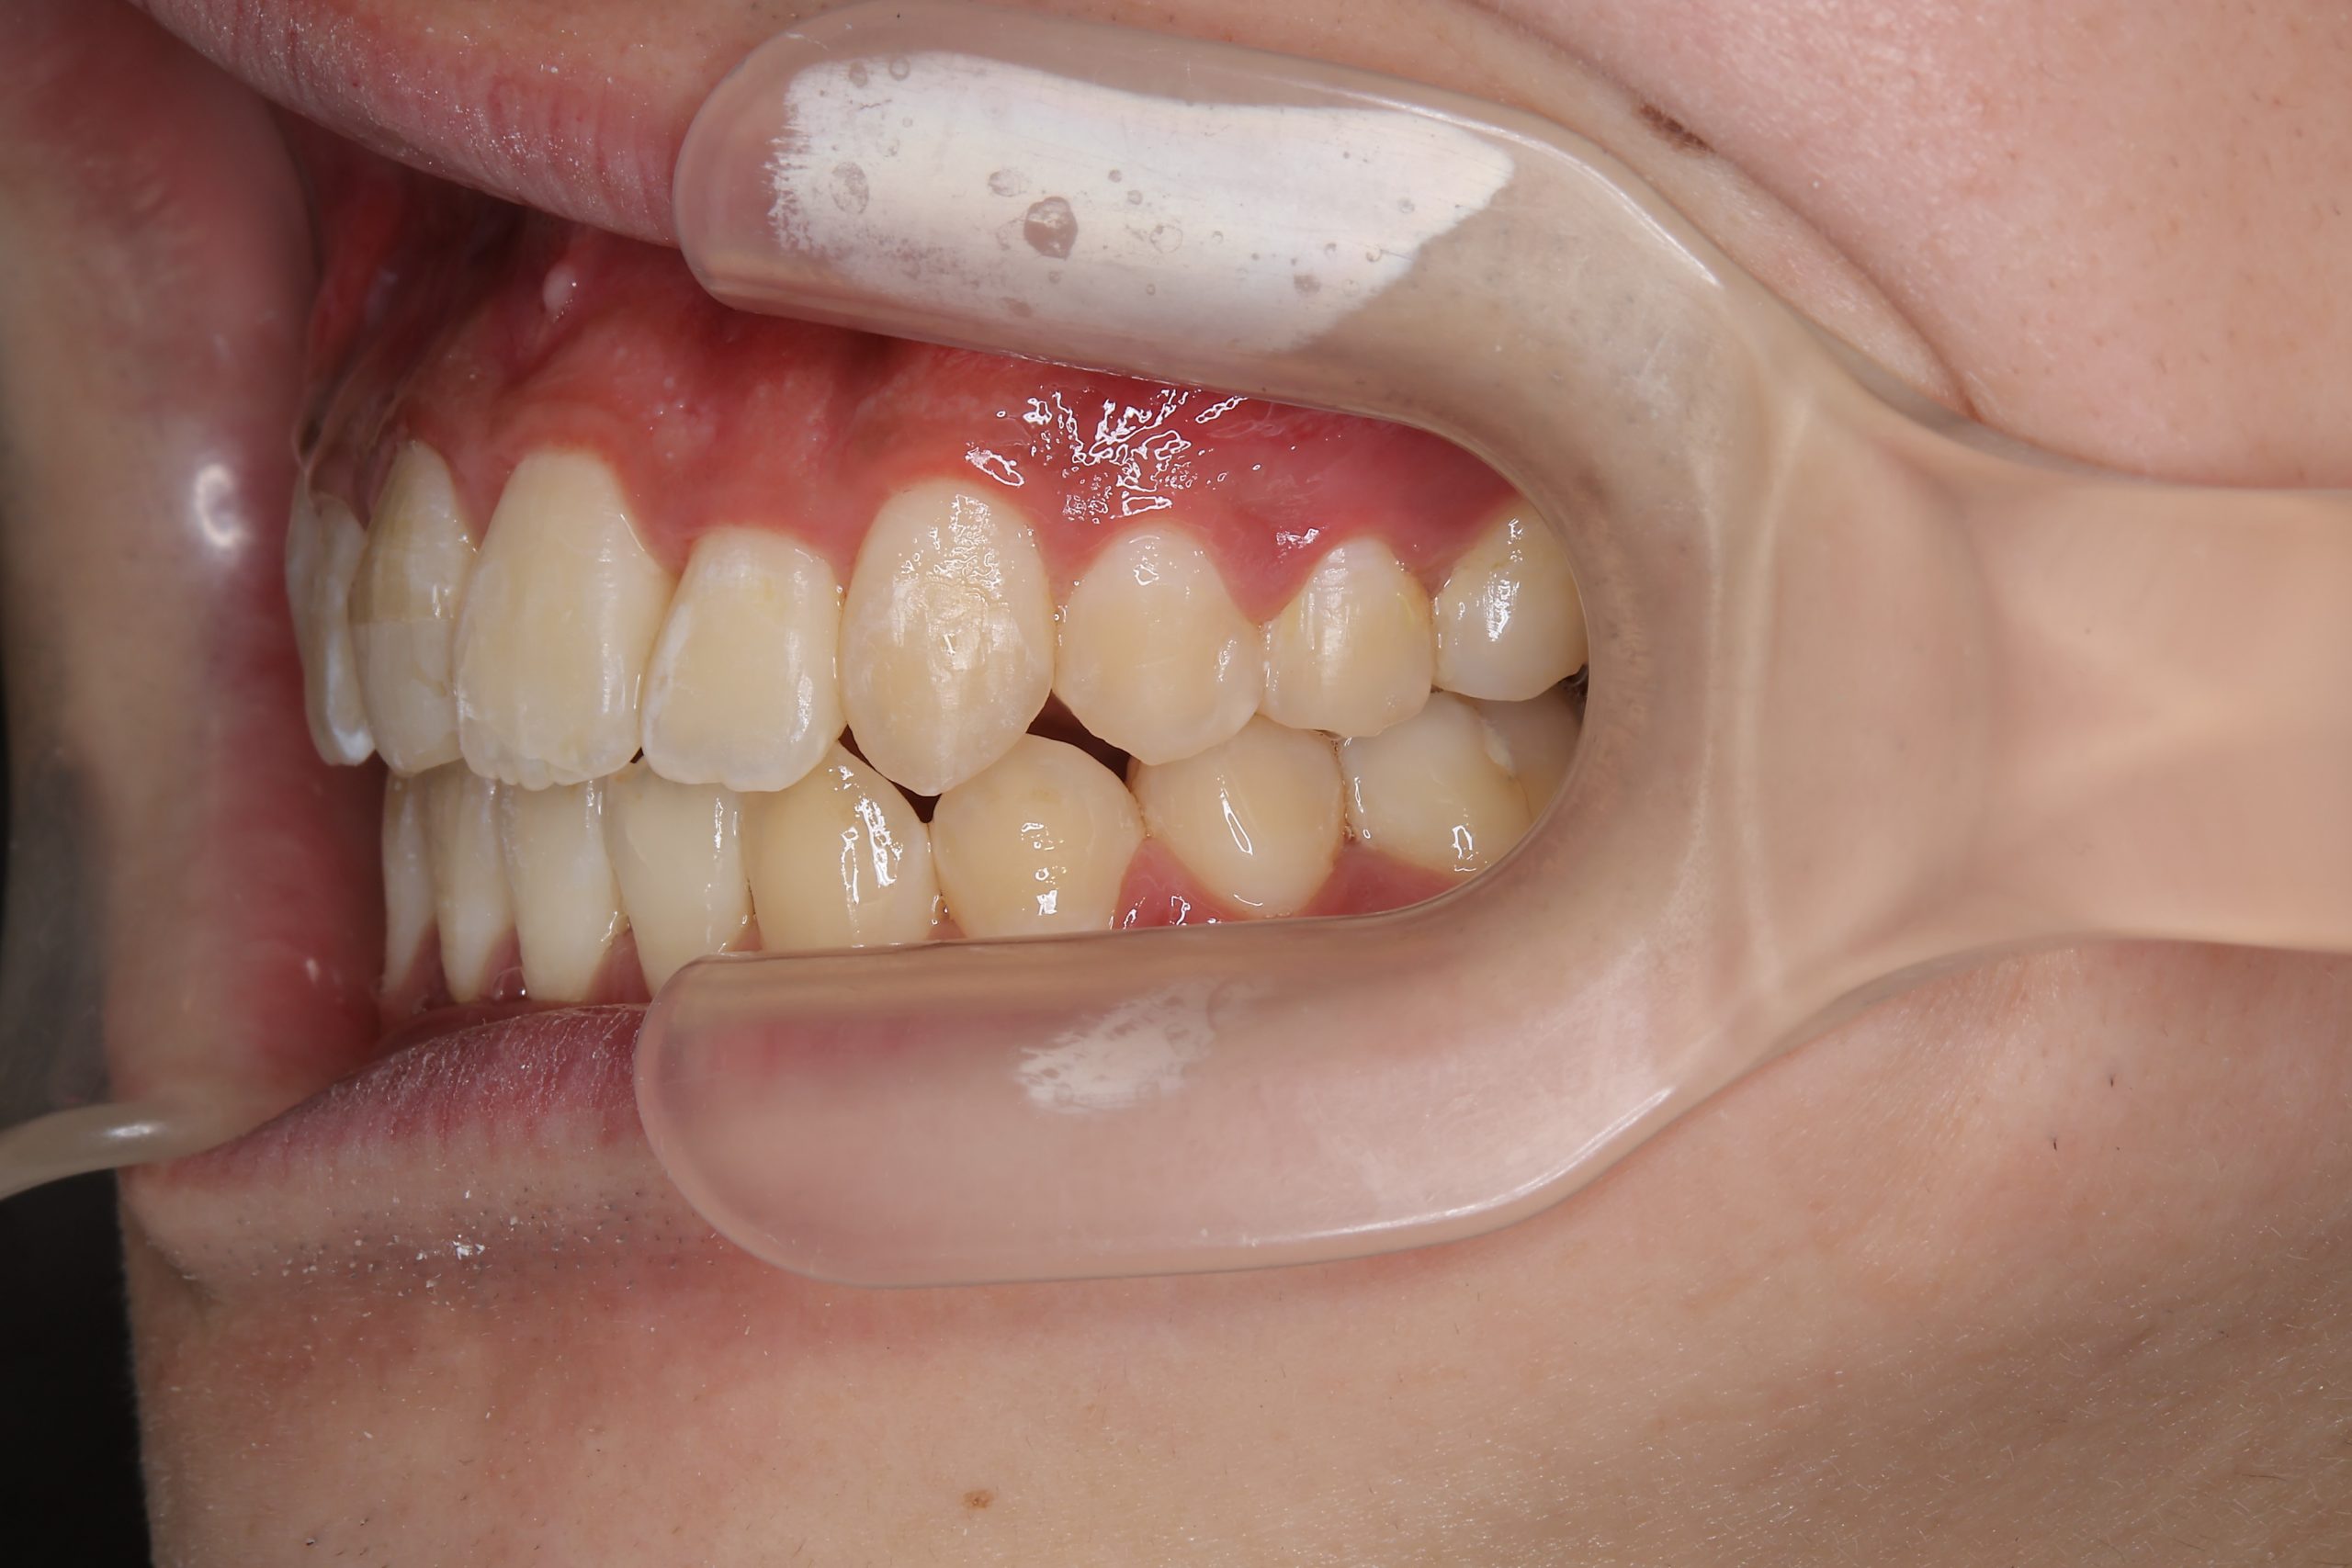

アフター

ワイヤー矯正治療|症例_037

主訴 前歯が少し前に出ている|鼻づまり

施術内容 MSEと下顎リンガルアーチを用いて上下顎骨を拡大した。

その後をマルチブラケット装置を用いて非抜歯で歯牙を配列し、良好な咬合を獲得した。

治癒期間 1年6か月間